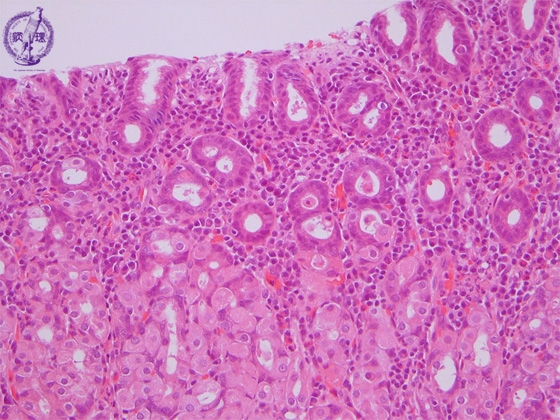

Microscopic view (H&E stain, intermediate power): Chronic gastritis. The surface epithelium shows chronic, predominantly lymphoplasmacytic inflammation while foveolar crypts show regenerative change.